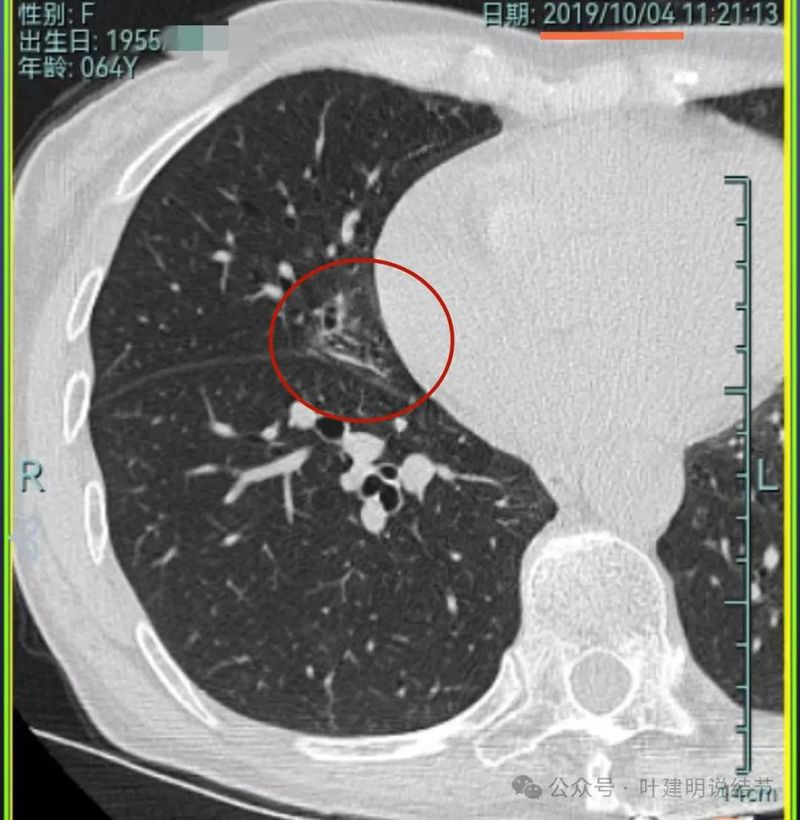

先来看2019年时的影像:

病灶1:右上叶磨玻璃密度结节,略偏长条状,有微小血管进入,轮廓与边界较清。

病灶2:右下叶磨玻璃结节,边缘不平毛糙,没有实性成分,轮廓与边界较清楚。

病灶3:右中叶混合密度结节,有分叶征,有收缩力,整体轮廓与边界清。

病灶4:右中叶伴钙化结节,考虑良性。

病灶5:右中叶磨玻璃病灶,轮廓与边界稍显模糊,灶内有支气管扩张的样子,贴叶间裂较近。

病灶6:左上叶淡磨玻璃结节,轮廓较清,密度较低。

病灶7:左下叶胸膜下结节,大部分磨玻璃密度,只是不太均匀,说不上明显的实性成分,整体轮廓与边界较清。此灶当年已经切除,从术后影像来看,大概是段切除可能性大些。